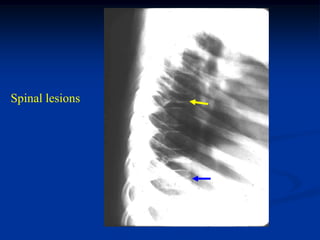

6 year female with HSC disease skull, spine and pelvis

Pelvis

Spinal lesions

Biopsy photomic